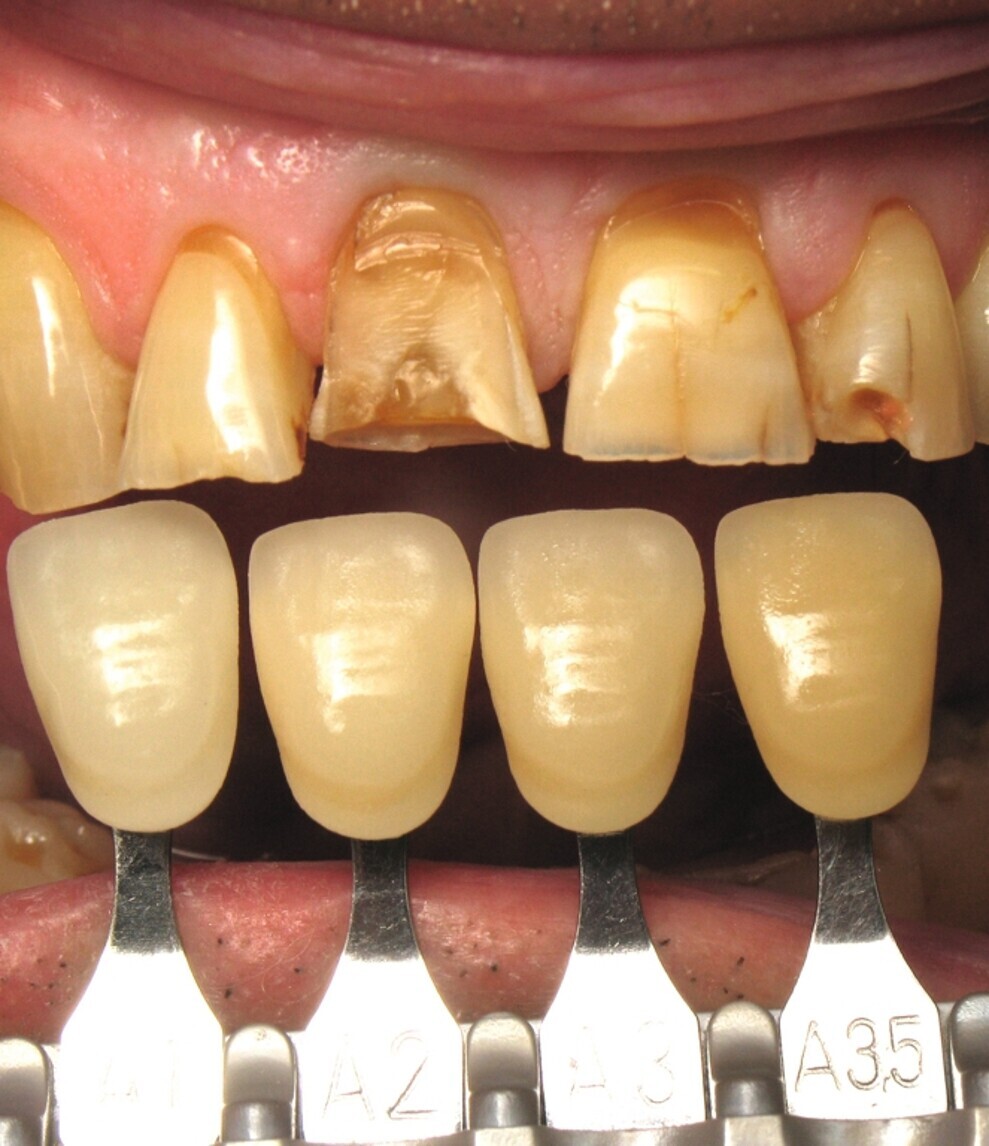

Fig. 10 : Teinte dentaire préopératoire.

Une heure avant, la figure 10 montre un véritable patchwork de teinte dentaire. On constate une translucidité du bord libre, une saturation cervicale, des fêlures, des restaurations absentes, et une fracture coronaire complexe de la dent 11. Tous ces éléments ont amené les dents à réagir, en construisant au cours du temps, de la dentine réactionnelle a l’origine des nombreuses variations de teinte.